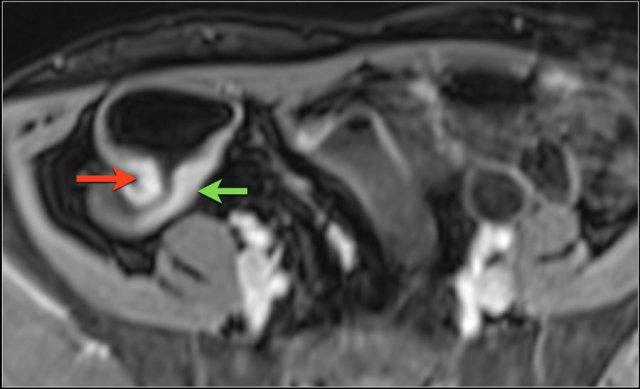

Hình ảnh cho thấy hồi tràng cuối với kiểu ngấm thuốc đồng nhất, mức độ vừa (mũi tên xanh lá) và mạnh (mũi tên đỏ) trên hình ảnh T1 axial sau tiêm thuốc tương phản từ.

Hình ảnh là ảnh T1 sau tiêm thuốc tương phản từ với kiểu ngấm thuốc niêm mạc tại hồi tràng cuối (mũi tên).